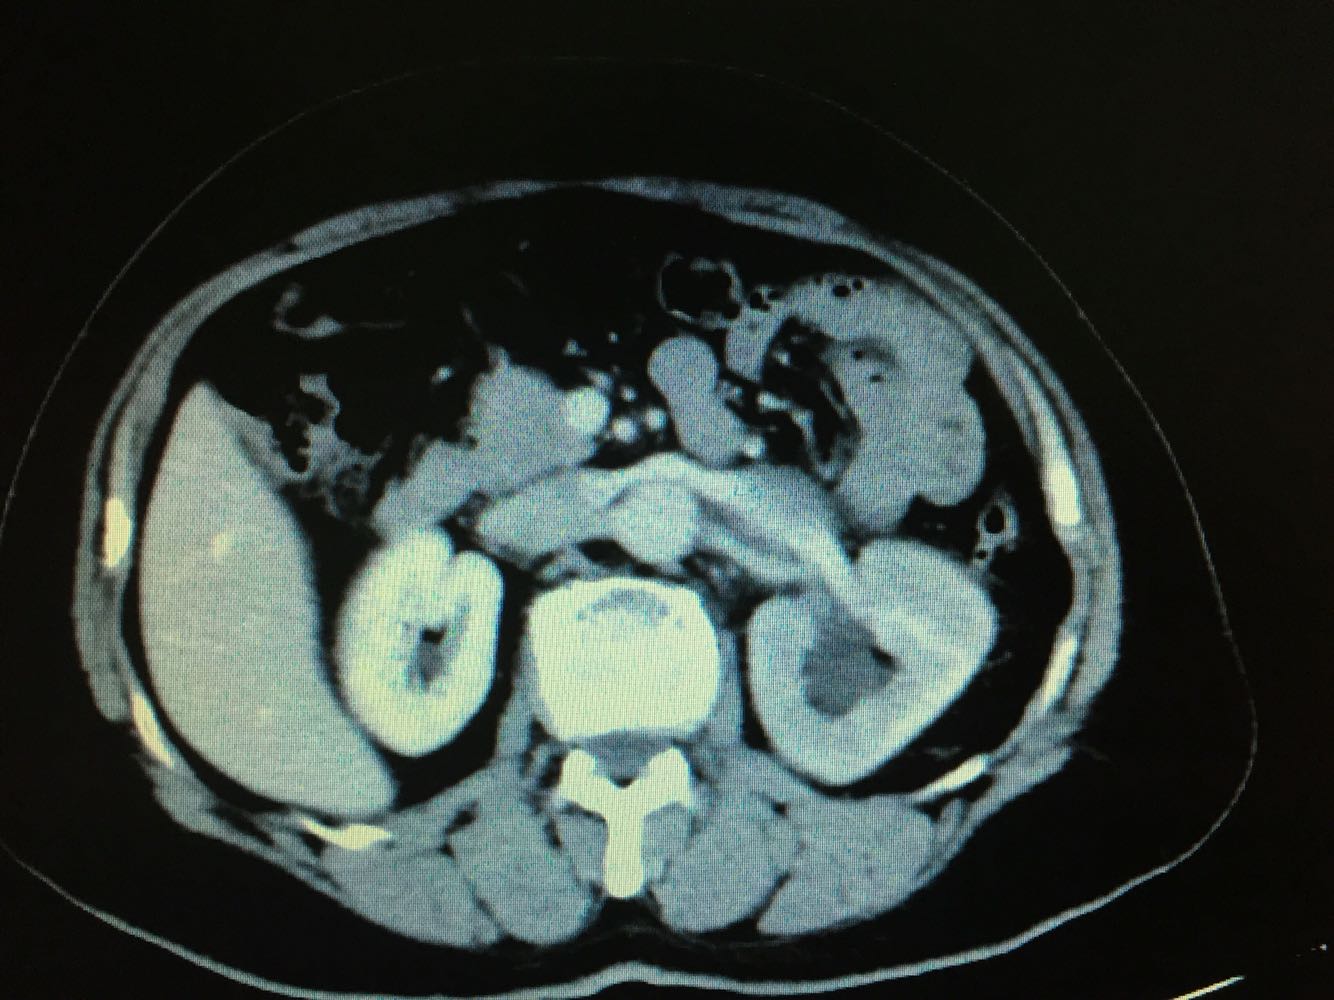

CT提示,左侧肾门处雪人样占位,包裹左肾静脉,左肾积水,与胰腺及左肾关系密切,血常规,肝肾功未见明显异常,GFR左侧27,右侧58。

诊断,左侧腹膜后占位:淋巴瘤?或者淋巴样增生?,侵犯周围器官组织?